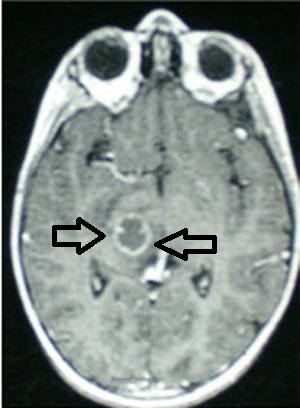

“Pelin bize ilk defa 16-17 sene önce geldi. Beyninin tam orta bölgesinde apse saptandı. Üst solunum yolunda, burunda ve sinüslerde olan bir enfeksiyon ilerlemiş ve beyninde apseye yol açmıştı. Tedavi için önce apseyi ince bir iğne ile boşalttık. Ameliyatın ardından antibiyotik tedavisiyle enfeksiyonu atlattı. Ama apsenin bulunduğu yerde yarattığı tahribat nedeniyle sol kolunda istemsiz hareketler olmaya başladı. Rubral tremor dediğimiz bu durum hem çocuklarda hem de erişkinlerde çok nadir görülen bir hastalık aslında. Yaklaşık 2 yıl ilaç tedavisi gördü. Ama fayda görmedi. O yaştaki bir çocukta beyin pili endikasyonu çok rastlanan bir şey değildi ancak başka seçeneğimiz yoktu. Diğer cerrahi yöntemler yaşı nedeniyle komplikasyon açısından riskli olabilirdi. 13 yaşındayken ilk beyin pilini taktık. Bu hastalarda pilden sürekli olarak beyne yerleştirilen elektrotlara bir elektrik akımı verilir. Dolayısıyla pilin belli bir  ömrü vardır. Bazı hastalarda 2-3 yıl, bazılarında 5-6 yıl gider. Ama pili mutlaka değiştirmek gerekir bu sürelerden sonra. Köprücük kemiğinin altından küçük bir ameliyat ile pil değişim işlemi yapılır.”

Sabancı Üniversitesi’nde Toplumsal Duyarlılık Projesfi ekibinde çalışan ve aynı zamanda gezi ve yemek üzerine blogger’lık yapan 28 yaşındaki Pelin Köroğlu’nun hayatı, 9 Mart 2003’de aniden ateşlenmesiyle alt üst oldu. Henüz 11 yaşındaydı ve o kadar şiddetli bir baş ağrısı çekiyordu ki ailesi acile götürdü. Ertesi sabah beyninde apse oluştuğu anlaşıldı. Acilen ameliyata alındı ve apse boşaltıldı. Birkaç gün sonra ikinci kez ameliyat edildi. Soğuk algınlığı ve sinüzite bağlı gelişen beyin apsesini atlatsa da kısa bir süre sonra sol tarafında istemsiz kasılma ve aşırı titremeler baş gösterdi. Yaşı çok küçük olduğu için fizik tedavi ve ilaçlarla tedavi sağlanmaya çalışıldı. Ancak 2 yıl süren ilaç tedavisinden hiçbir fayda görmedi. Pelin henüz ilköğretim öğrencisiydi ve hastalığı yüzünden tahtada ders anlatamamaya, elinde defter kalem dahi tutamamaya başlamıştı. Hatta geceleri uyurken onunla beraber yatan annesini uyandırmamak için, sol kolunu bacaklarının arasına sıkıştırmak zorunda kalıyordu. Sonunda doktorları Pelin’e beyin pili takılmasına karar verdi. 2005’de henüz 13 yaşındayken Türkiye’de beyin pili takılan ilk çocuk hasta olarak hayatı bir kez daha değişti ve kibrit kutusu büyüklüğündeki minicik bir cihaz sayesinde eski haline kavuşabildi. Ancak “pil” macerası bununla da bitmedi.